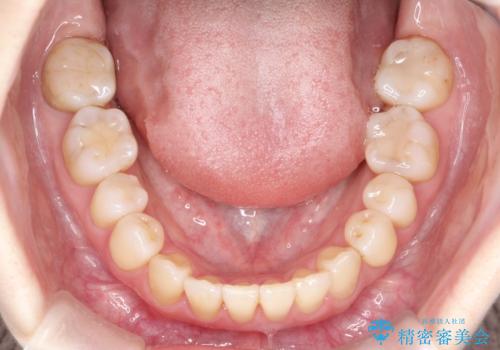

初診時の歯並びの状態としては、上下ともに前歯部中心としたの中等度のがたつき(叢生)があり、全特に左上の前歯は1本だけ引っ込んでおり、犬歯は外に飛び出した状態でした。

抜歯は行わず上顎の奥のスペースを利用して歯をスライドする方法の他に歯列弓の拡大やディスキング(歯と歯の間の隙間を作る処置)を行い叢生を改善しましています。

歯の大きさの不揃いが原因の正中のズレは、ディスキング量を調整することで合わせました。